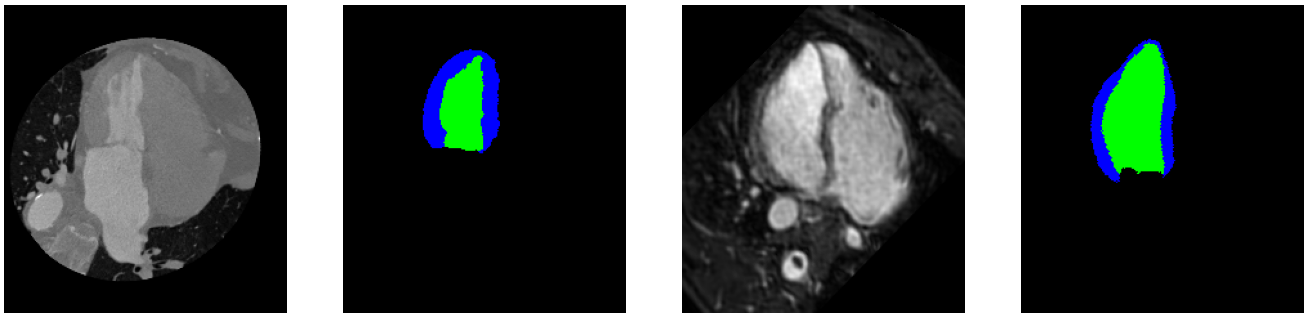

The second DA dataset used in this experiment was a modified version of the MM-WHS dataset [20] for 3D multi-modal whole heart segmentation, created by Wu and Zhuang (2020). This modified MM-WHS dataset contains 20 cases of labelled CT heart scans, with 16 2D slices from the long-axis view centered on the left ventricle [3]. It also features 32 unlabelled cases of 16 similar slices for CT. Additionally, this dataset features 20 cases of labelled MR heart scans and 26 unlabelled cases with the same slice configuration as the CT examples. This data features ground truth labels for the Myocardium (Myo) and the Left Ventricle (LV) in both the labelled CT and MR scans, making this a multi-class segmentation problem. An example of the dataset for the MR and CT scans can be seen in Figure 3. As can be seen in Figure 3, there is a clear domain shift between the CT and MR heart scans, with a very noticeable difference in pixel intensity distribution and overall structure/shape.

Refer to caption

Figure 3: CT (first from left) and MR (third from left) 2D slices from the long-axis view centered on the left ventricle, from the MM-WHS Dataset. Accompanying LV and Myocardium labels shown in green and blue respectively to the right of their respective images.